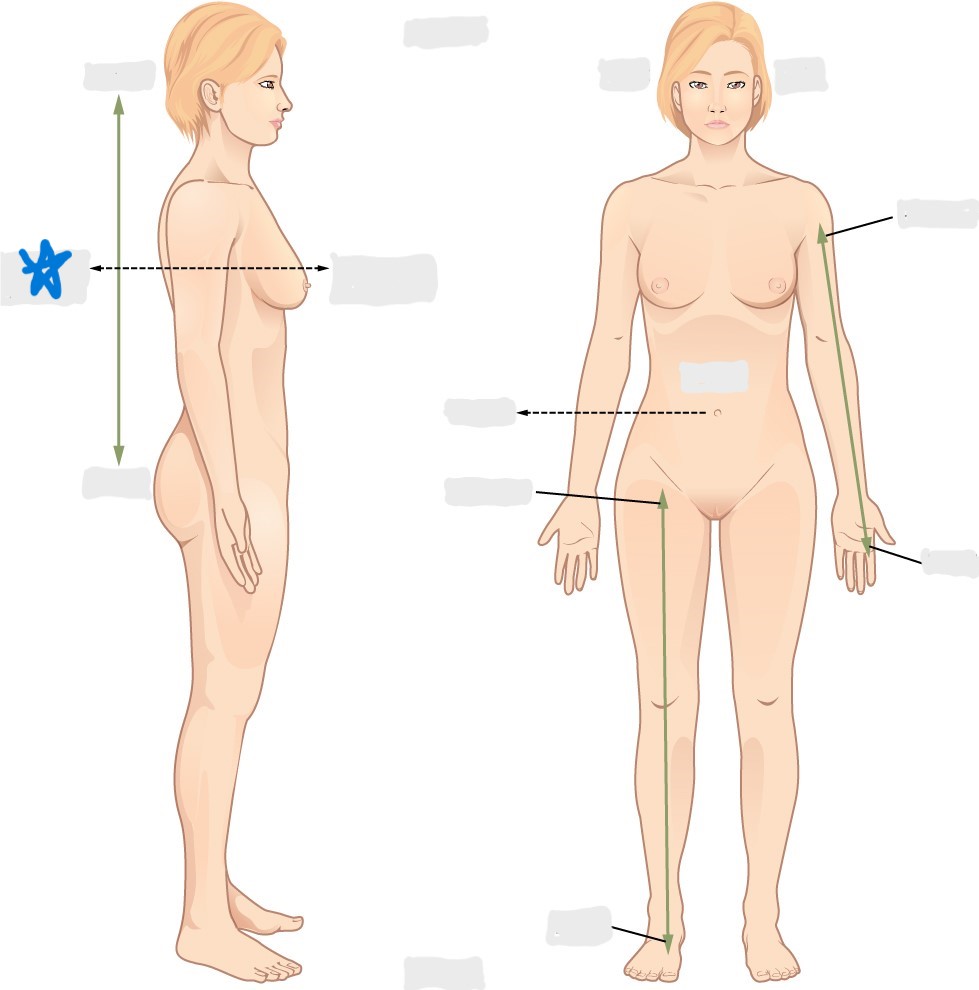

dorsal/posterior

ventral/anterior

lateral

medial

distal

proximal

superior

inferior